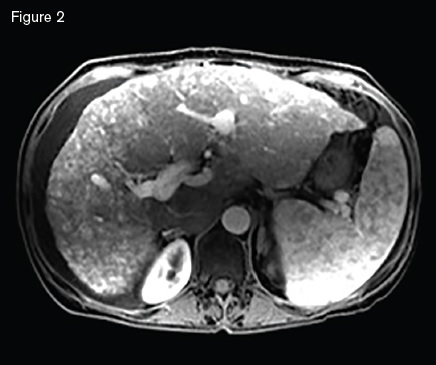

Magnetic resonance image showing a macronodular liver with diffuse arteriovenous malformations s involving both hepatic lobes, ascites, and splenomegaly.

A 51-year-old woman with HHT was referred for management of recurrent epistaxis, GI bleeding, iron deficiency anemia, large bilobar hepatic AVMs, and worsening ascites. Gastric AVMs were previously managed with endoscopic argon plasma coagulation. She required regular intravenous iron and occasional blood transfusions to maintain a hemoglobin of seven to 10 g/dL. Elevated liver enzymes two years earlier prompted an ultrasound that demonstrated hepatic AVMs. Magnetic resonance imaging (Figure 2) demonstrated a macronodular liver with diffuse AVMs involving both hepatic lobes, ascites, and splenomegaly. Angiogram demonstrated large hepatic arteries with shunting primarily from hepatic artery to portal vein (Figure 3). She primarily reported weakness, dyspnea on exertion, and worsening ascites requiring weekly six- to seven-L paracentesis.